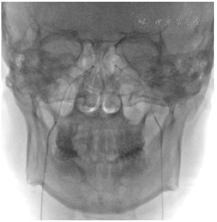

本例患者考虑为BIPSS假阴性的库欣病。患者垂体占位位于鞍内,岩下窦取血术中可见置管满意(图2),不考虑静脉结构或肿瘤位置变异。患者BIPSS基线ACTH水平在左、右岩下无明显差异,考虑BIPSS假阴性原因可能与肿瘤ACTH分泌无取血分侧差异相关。患者入院时、行BIPSS试验及外周DDAVP兴奋试验时的ACTH水平差异较大,故也有因肿瘤分泌ACTH波动导致的BIPSS假阴性的可能。